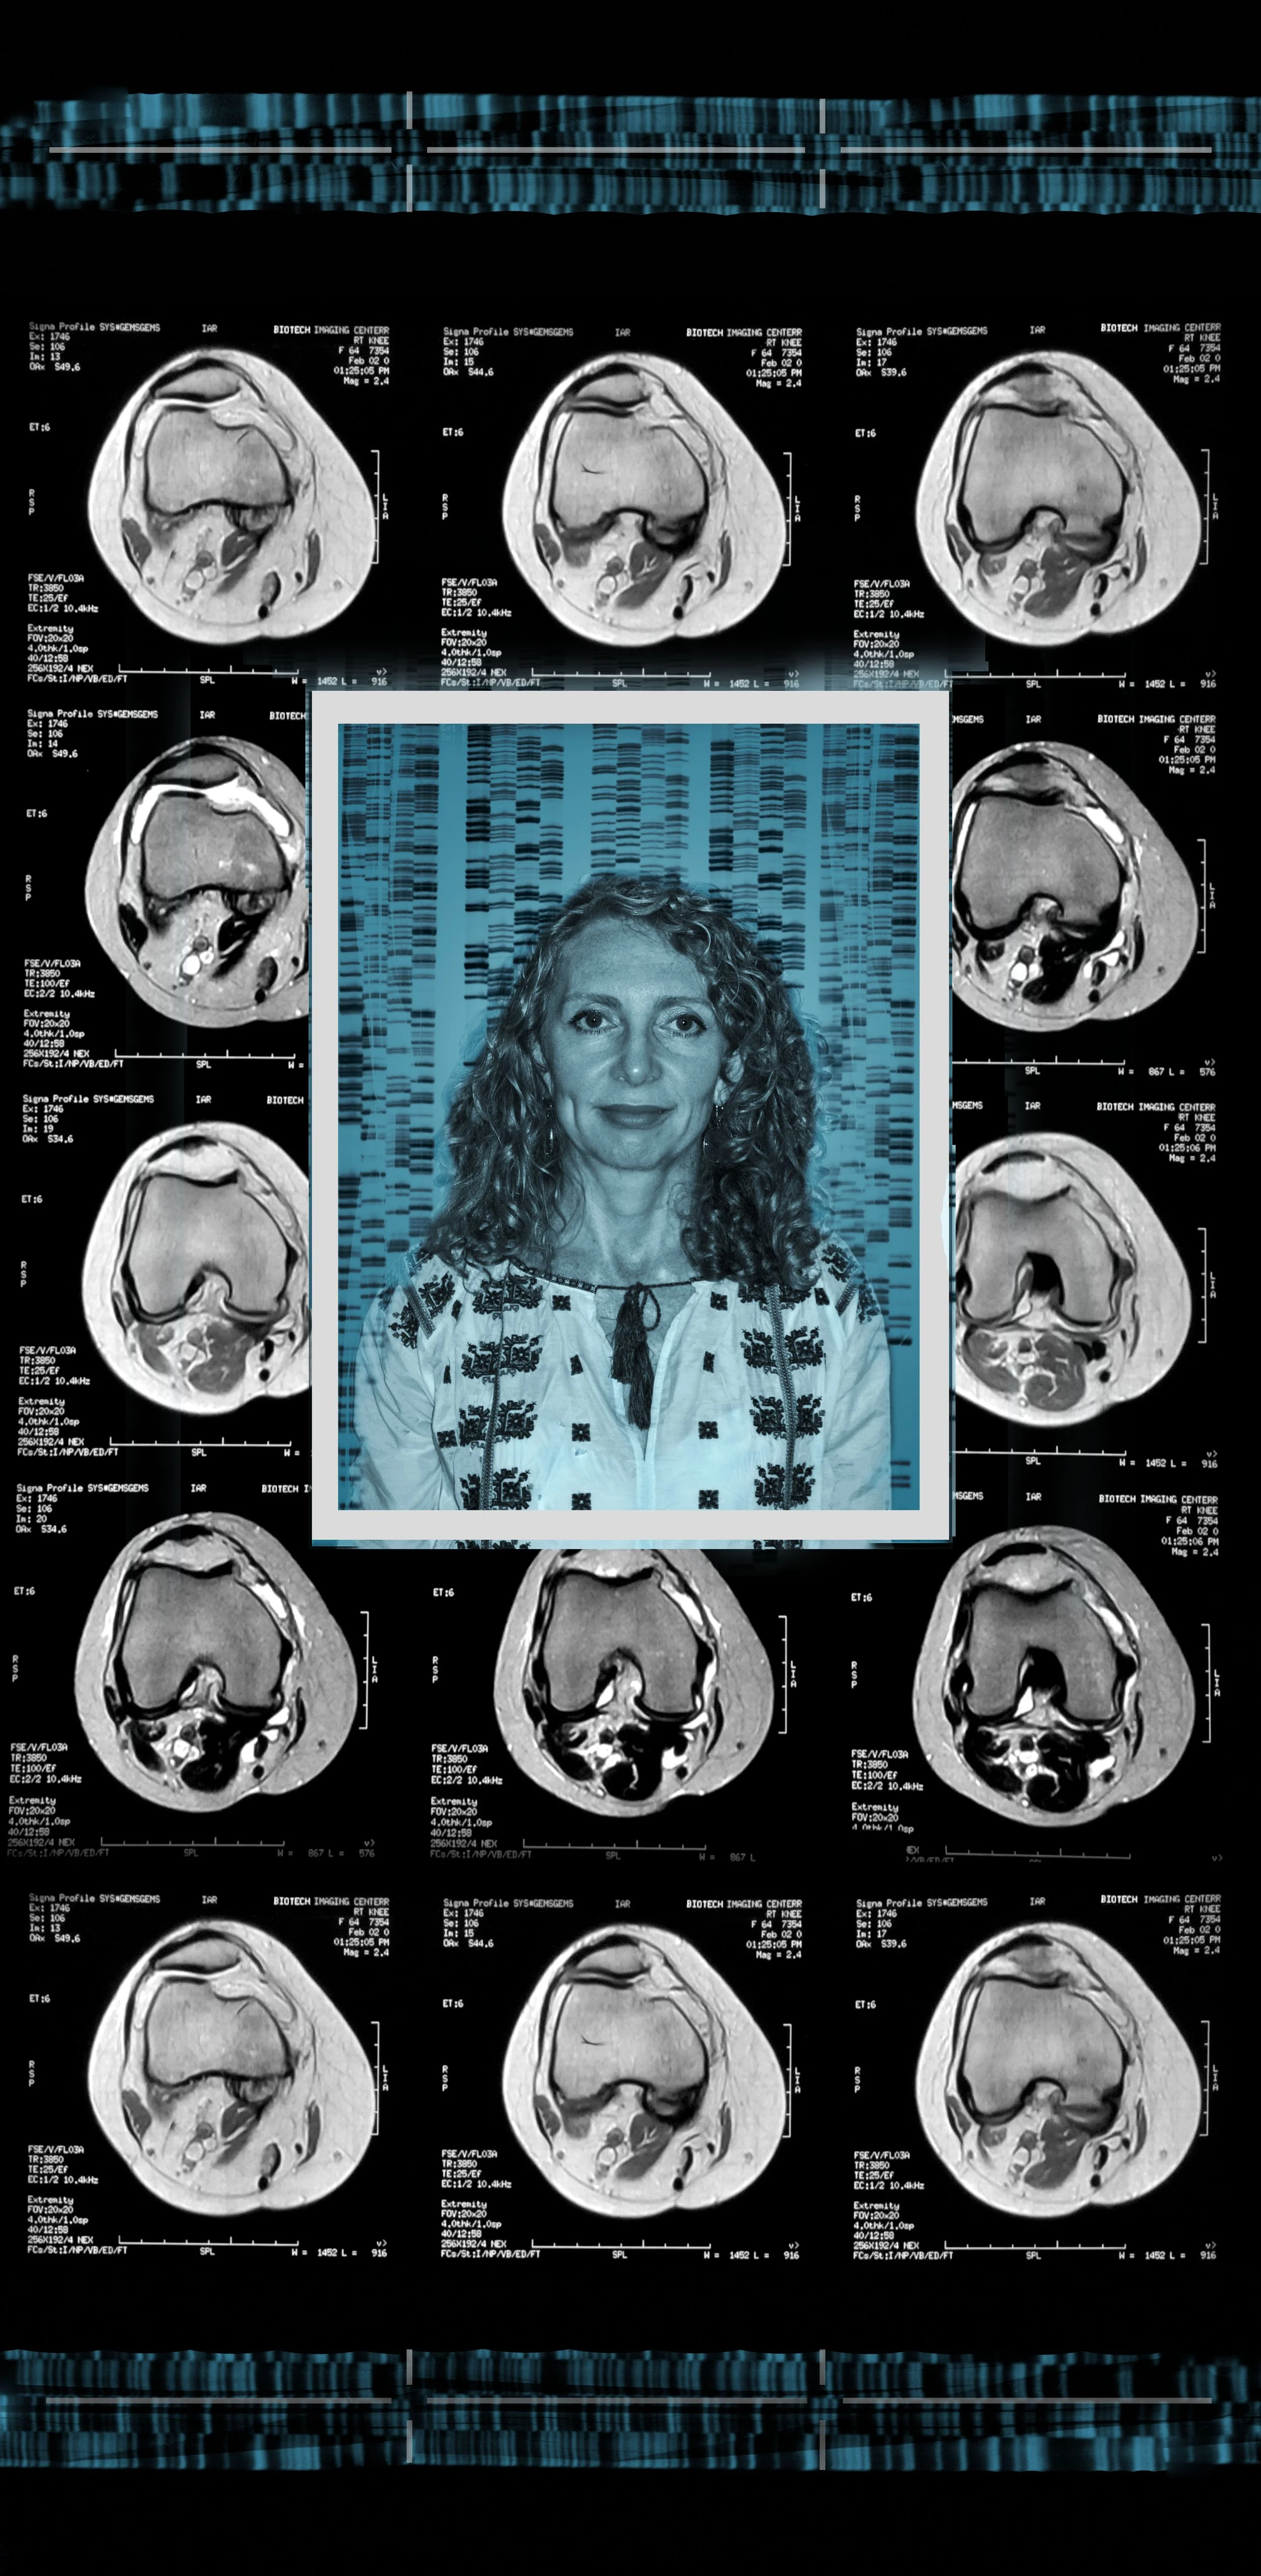

Comprising eight 47” x 23” backlit Plexiglas panels, each work features a portrait, often of individuals from diverse racial, ethnic, and cultural backgrounds. Surrounding these portraits are embedded CT scans, MRIs, and DNA sequencing gels. These medical images, reimagined as expressive symbols, evoke biological inheritance, invisible histories, and interior experience rather than clinical diagnosis.

Used metaphorically, DNA strands suggest ancestral continuity; CT scans and MRIs hint at the unknowable workings of body and psyche; ghostly anatomical forms recall trauma, resilience, and emotional scars. By pairing portraiture with interior imaging, the series questions how we perceive identity. Are we defined by surface appearance—skin, gender, dress—or by memory, genetics, and lived medical experience? Can scientific data be truly neutral, or does it reflect cultural bias and interpretation?

Luba 47” x 23”